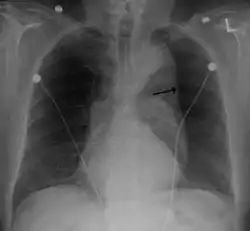

![]() أم دم الأبهر الصدري مع سهم يشير إلى الجانب الوحشي من شريان الأبهر. أم دم الأبهر الصدري مع سهم يشير إلى الجانب الوحشي من شريان الأبهر. | |